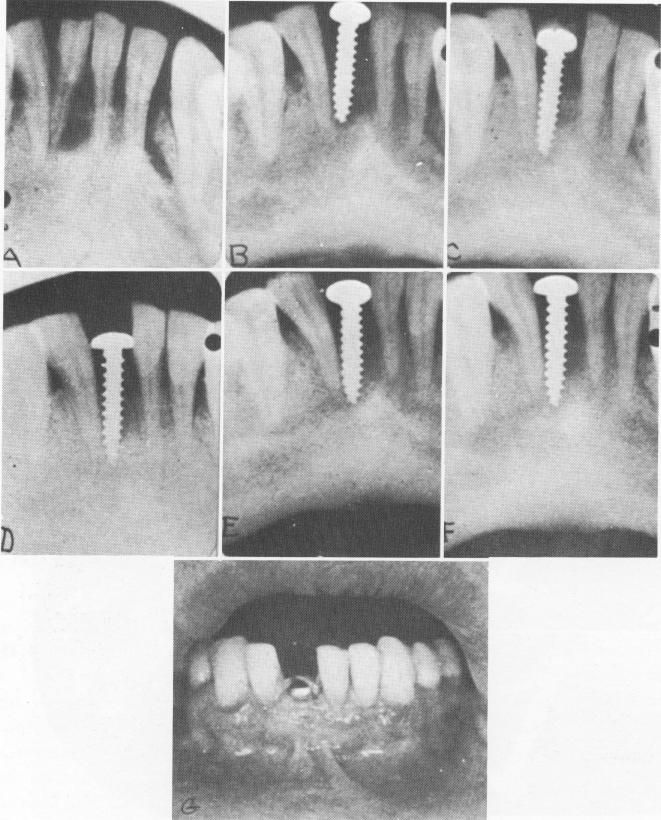

Fig. 5-7. A visual summary of a 1938 human implantation case done by the Strocks. A, The tooth to be extracted, with rarefaction about its apex. B, The implant, which was inserted in the socket about 3 weeks later. C through F, Bone condensation up to 8 months after insertion. G, The screw in position, showing the normal color and tone of the mucosa around the implant. (Courtesy A. E. Strock.)

some bony repair was obvious in x-rays and there was no evidence of disease. Although the screw was moderately firm buccolingually, it could be rotated.

Today we can better explain, in light of modern experience, the implant's looseness. Basically, because the shape of the screw permitted the widest diameter to protrude into the mouth, a great deal of soft tissue invagination probably occurred. This invagination, together with the closeness of the screw's threads, did not allow the bone to grow close enough to the implant to follow its shape and tightly secure it.